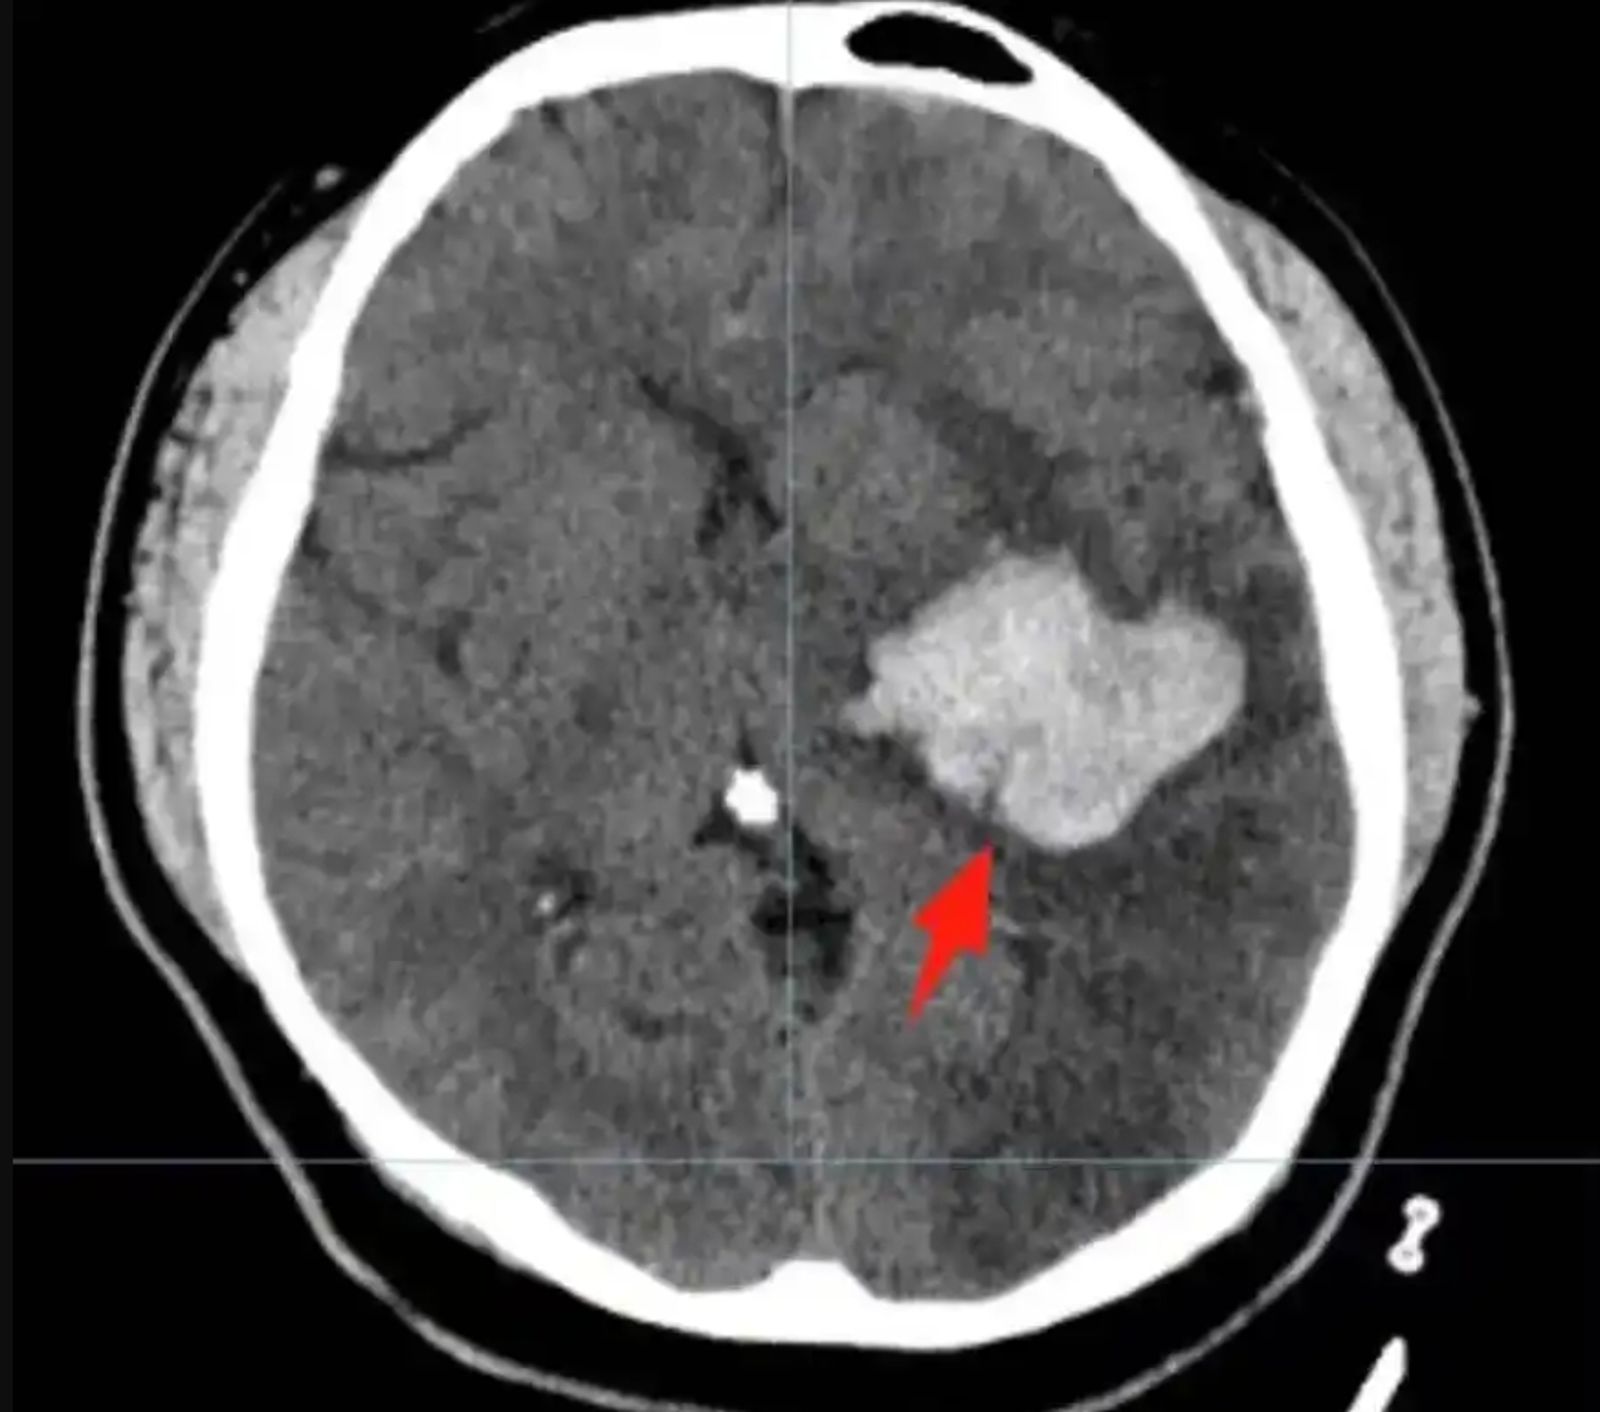

綜合中國媒體報導,丁男的母親說,兒子平時就愛吃燒烤、喝啤酒、熬夜、打遊戲,事發當天他加班完就去吃燒烤、喝啤酒,還打遊戲打到凌晨3點。當時丁男玩到一半突然頭暈目眩,右側肢體無力,被家人緊急送到深圳市寶安區石岩人民醫院急診科,當時他已經為嗜睡狀態,腦部照片子發現左側基底節區腦出血,出血量約20ml,隨即收住神經外科治療。

醫生一開始幫丁男採取控制血壓、護腦等保守治療,但是檢查卻發現出血量增加至38ml,病情加重。神經外科副主任醫師張岩睿向丁男的母親建議開刀治療,讓丁男的家人很害怕,不過醫生採用的是微創手術,不用開顱,所以家屬就同意了。